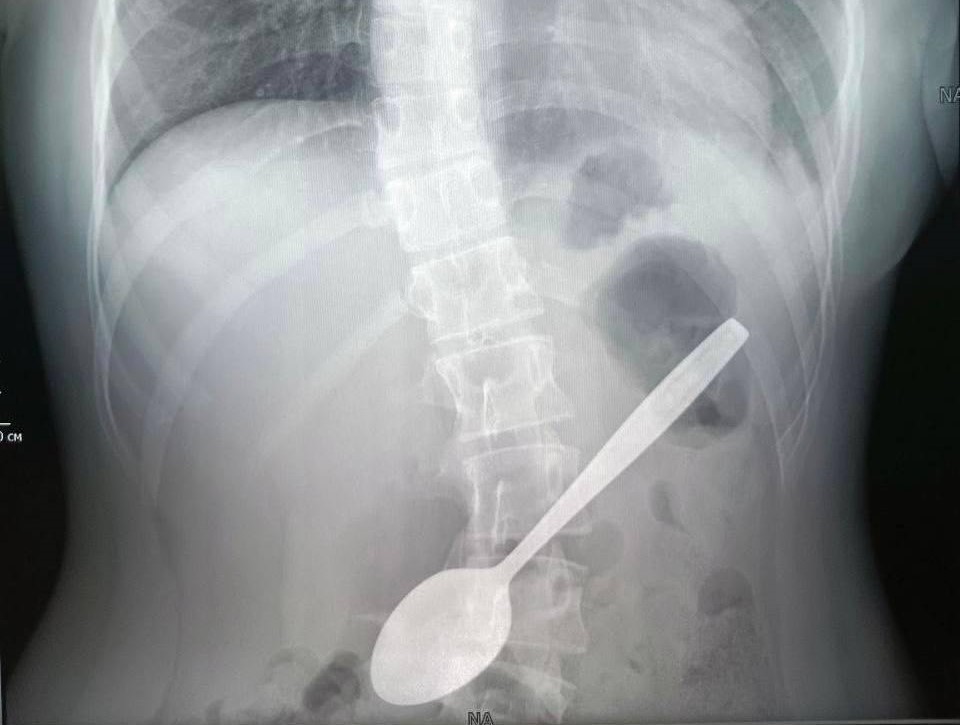

Незамедлительно врачи провели обзорную рентгенографию органов брюшной полости и подтвердили наличие инородного тела в проекции желудка.

— Во время операции с помощью видеоскопа мы осмотрели пищевод и желудок пациентки — пятнадцатисантиметровая ложка стояла в распорку: тонкой частью упиралась в стенку желудка, а широкой частью уходила в луковицу двенадцатиперстной кишки. Эндоскопической петлей мы извлекли ложку из луковицы двенадцатиперстной кишки, а после эндоскопическими щипцами по типу «крысиный зуб» протянули ее до глотки. После этого хирургическим зажимом мы полностью извлекли инородное тело из организма девочки. Операция длилась около часа и прошла успешно, — рассказала Дарья Степаненко врач-эндоскопист.